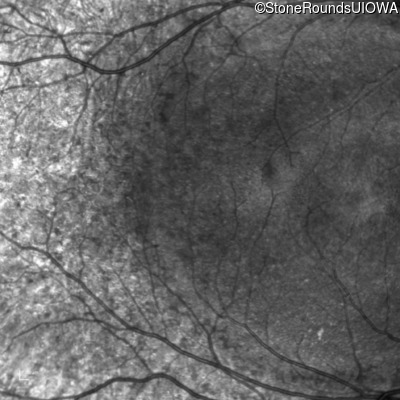

Infrared Fundus Photograph - Right - 20/25 -1

Exemplar